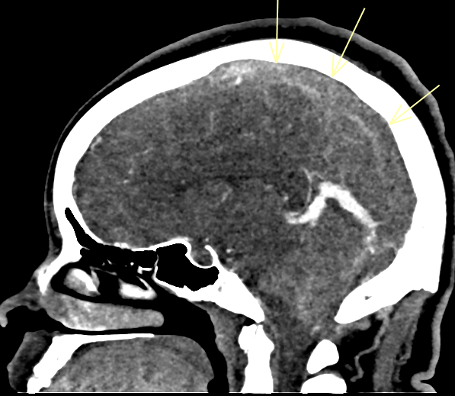

Diagnostic Testing. The patient’s CT brain imaging revealed a small amount of air in both frontal horns of the lateral ventricles (Figure 1). Her brain CTA revealed distension of the superior sagittal sinus (SSS), inferior sagittal sinus, transverse sinus, and vein of Galen and an extra-axial SSS defect (Figures 2-4). The initial report of the MRI brain with and without contrast redemonstrated trace pneumocephalus but was otherwise unremarkable. Later review after 10 days, revealed pachymeningeal enhancement, venous sinus distension, and a filling defect in the SSS suggestive of venous sinus thrombosis (Figures 5, 6). Her MRI of the cervical spine did not reveal another cause of neck pain, and her urine protein was negative.

Fig. 2. Short segment filling defect of the mid portion of the superior sagittal sinus.

Fig. 3. Coronal view shows intraluminal filling defect of the superior sagittal sinus.

Fig. 4. Axial view of the focal filling defect compatible with thrombus within the superior sagittal sinus.